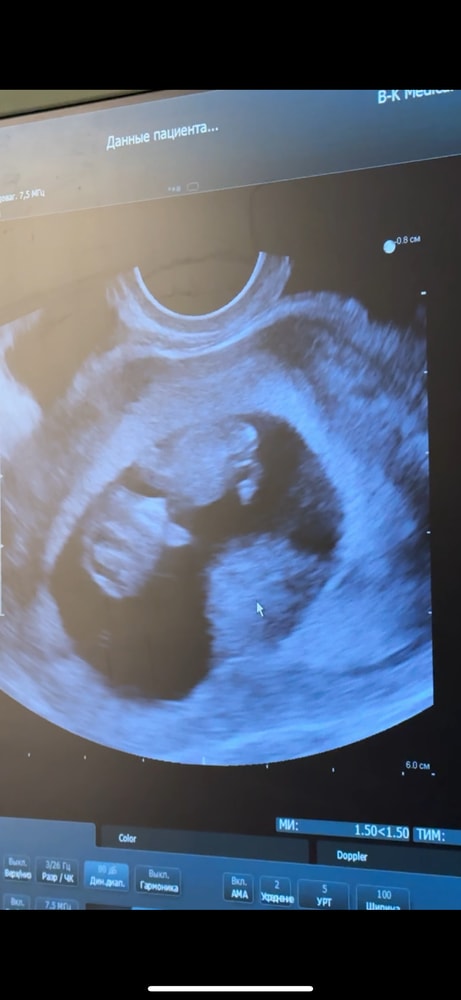

9 недель и 5 дней)) Изображение